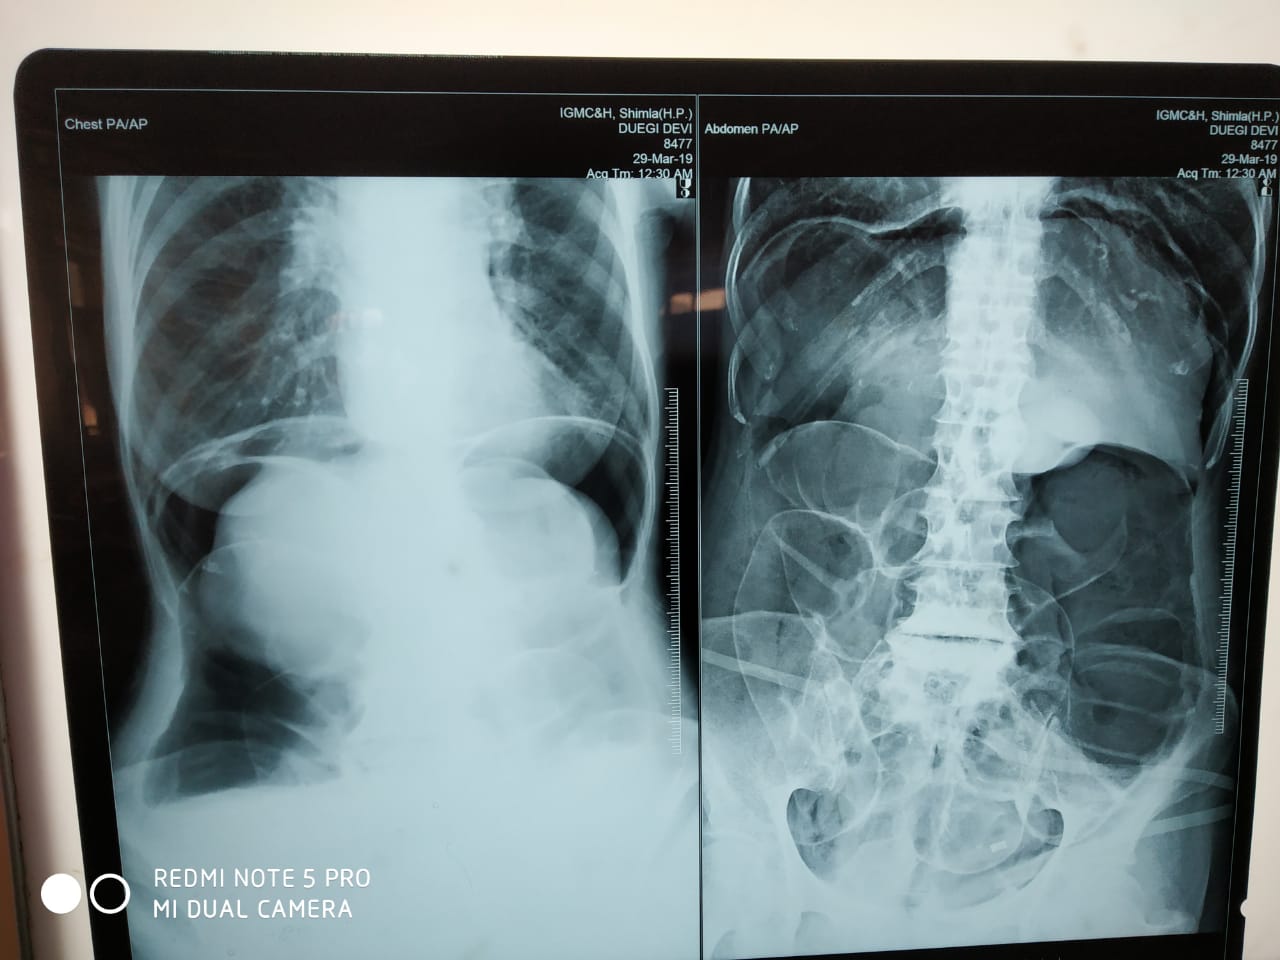

A plain abdominal X-ray showed a markedly distended large bowel

Figure 1: Dilated Large Bowel Loops

Radiologic imaging may be abnormal and detect CV in 45–56% of the cases [5] .Plain abdominal x-ray is highly sensitive for the diagnosis of CV with the characteristic “coffee bean“ sign deformity, its apex pointing to the left upper quadrant [9]. Other findings commonly seen are cecal dilatation (98−100%), single air–fluid level (72–88%), small bowel dilatation (42–55%), and absence of gas in the distal colon (82%). CT is more sensitive and specific for diagnosing CV and detecting complications [10].